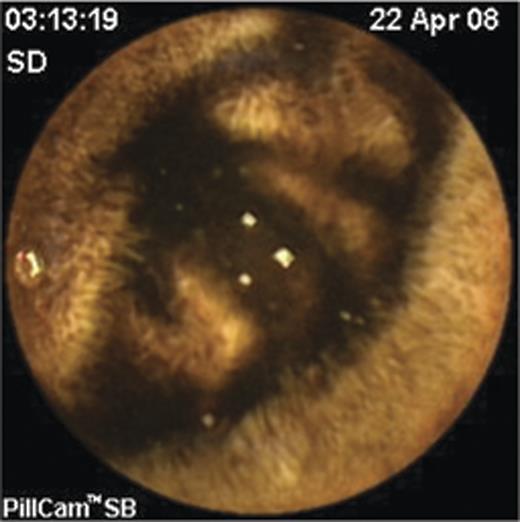

The laboratory tests showed a hemoglobin level of 6.5 mg/dl, urea 130 mg/dl and creatinine of 3.5 mg/dl. The patient was treated conservatively. An isotopic study with Tc-99 did not reveal any bleeding source. Computed tomography was initially interpreted as normal. A VCE study was performed that identified a submucosal bulge with a central ulceration in the proximal third of the small bowel (Fig. 1). More distally in the small intestine melena could be seen by the capsule (Fig. 2). Revision of the CT scan confirmed the VCE finding and showed a lesion of fat density in jejunum.

Videocapsule endoscopy image of melena within a more distal small bowel loop.